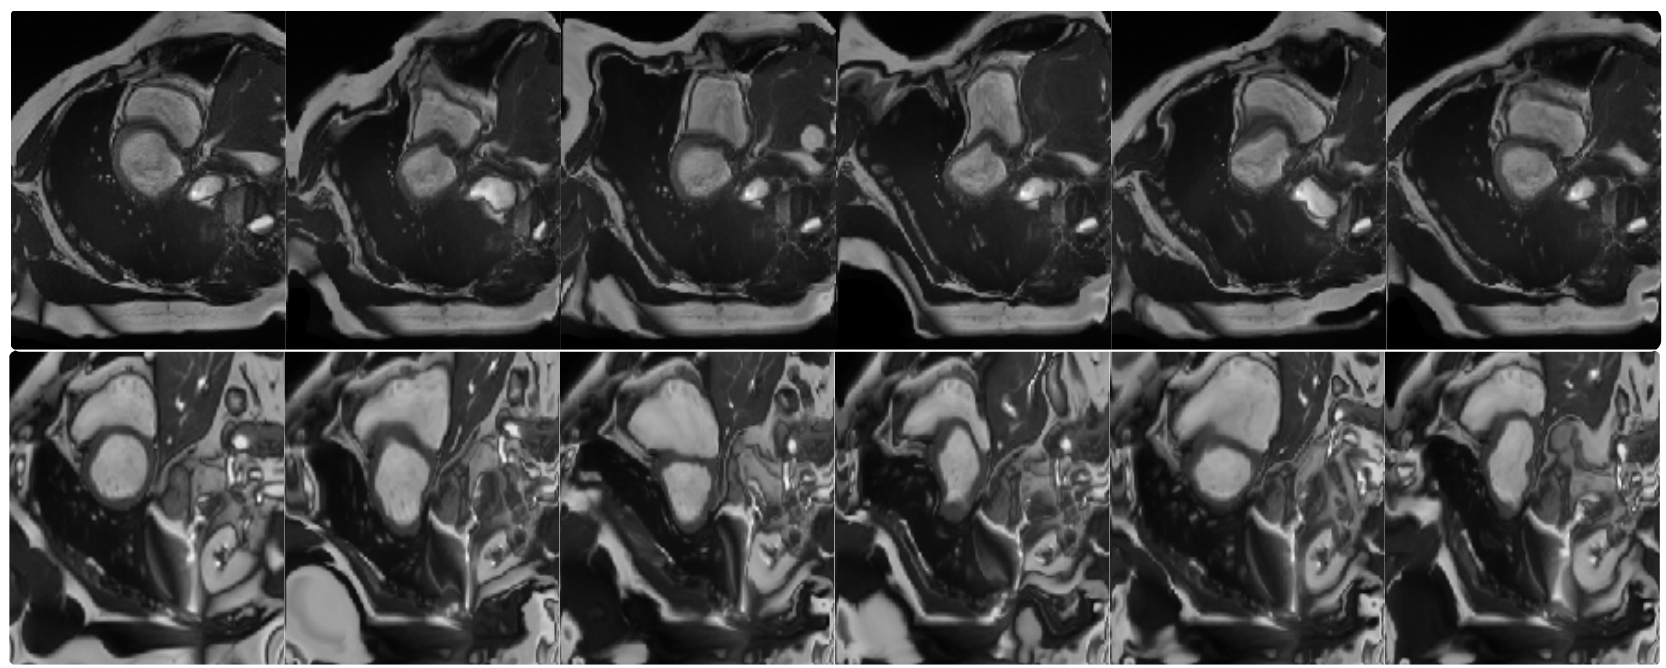

An exploration of 2D and 3D deep learning techniques for cardiac MR image segmentation

Christian F. Baumgartner, Lisa M. Koch, Marc Pollefeys, Ender Konukoglu

International Workshop on Statistical Atlases and Computational Models of the Heart, 111--119 (2017)

preprint URL